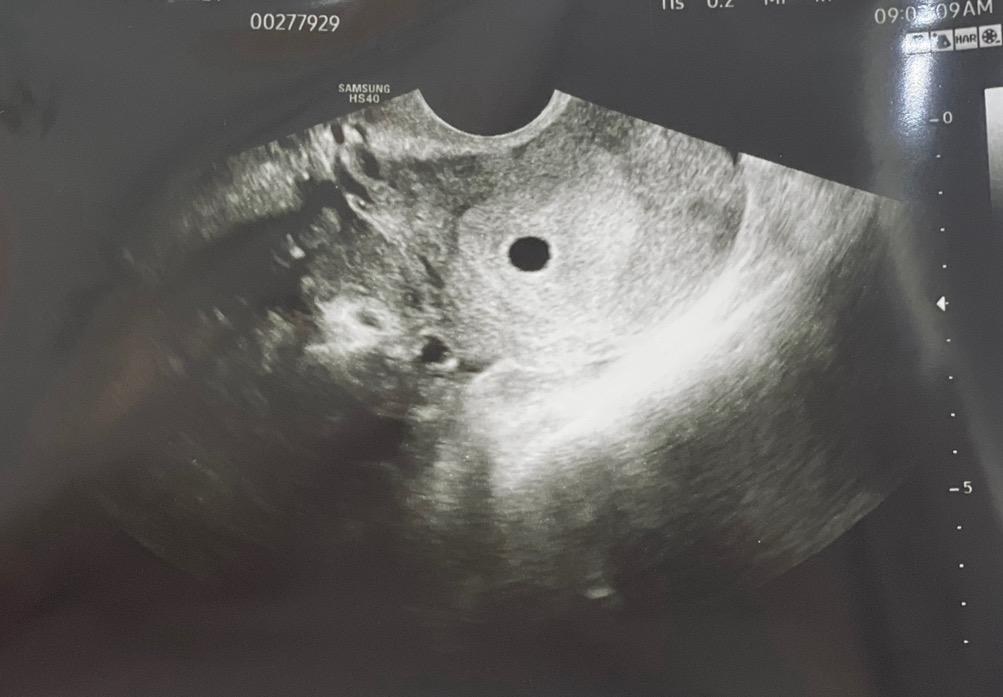

4주6일차 지난주 금요일에 드디어 아기집 보고 왔어요!! 크기는 0.5cm 정도 되는 것 같고 5주0일 진단(?)받았습니다 ㅎㅎㅎ 2주 뒤에는 심소 들을 수 있겠죠?? 심소 들을 때는 남편도 같이 병원에 데리고 가야겠어요👶🏻 걱정이 많았는데 두 눈으로 아기집을 보고나니 기특하고 괜히 걱정한 것 같아 마음이 많이 놓이네요! 앞으로도 아가 믿고 마음 편히 지내야겠습니다🧡 (앗 그런데 저기 자궁 왼쪽에 작은 검정 구멍(?) 보이는 부분이 뭔지 혹시 아시는 분 계실까요?,? 쓸데없는 탐구정신이 .... ㅎㅎㅎ 궁금하네용)